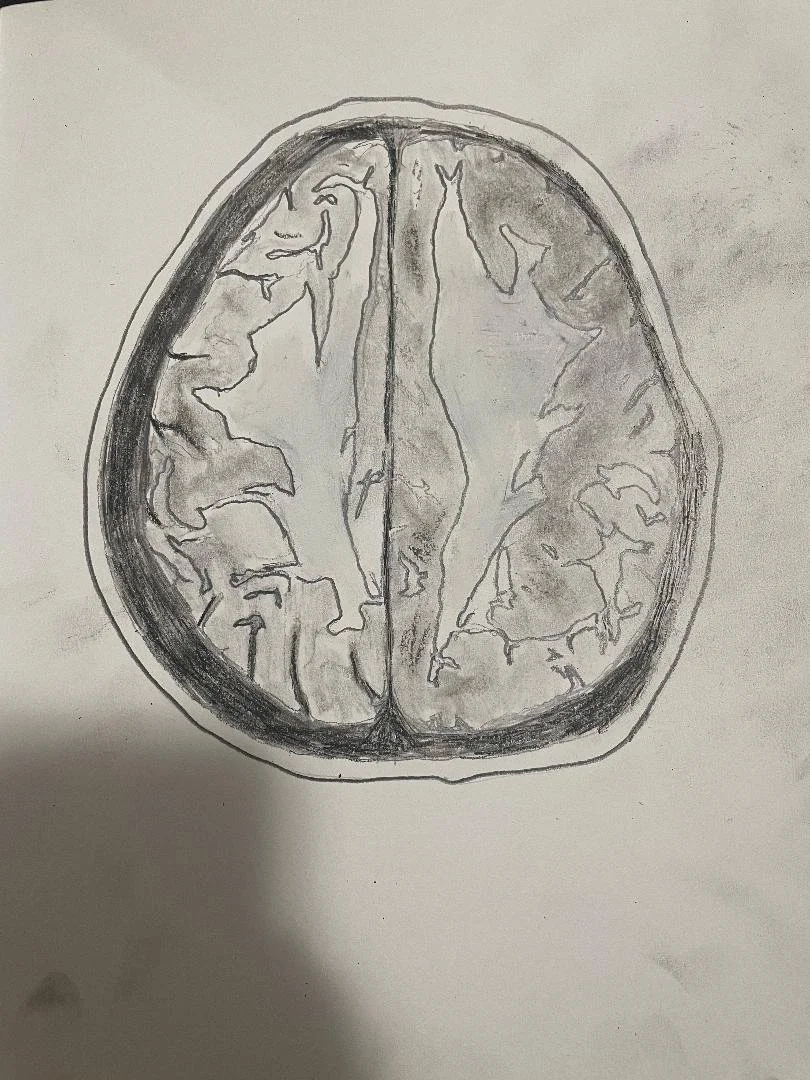

Harlequin sign - bilateral